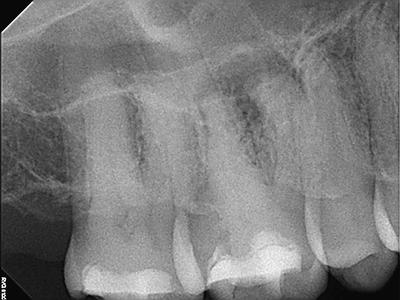

Radiographic Examination:

Tooth # 3 exhibits severe pulpal calcification, periapical radiolucencies associated with all 3 roots and severe dilaceration of the mesiobuccal root.